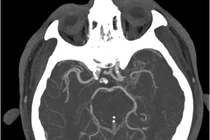

Đột quỵ nhồi máu não là căn bệnh cấp tính nguy hiểm với tỷ lệ mắc cao, nếu không được phát hiện sớm, điều trị đúng có thể gây di chứng thần kinh kéo dài, thậm chí tử vong.

Điều trị thuốc tiêu huyết khối đường tĩnh mạch là một trong những kỹ thuật điều trị triệt để đối với người bệnh đột quỵ nhồi máu não cấp trong 4 giờ 30 phút đầu.